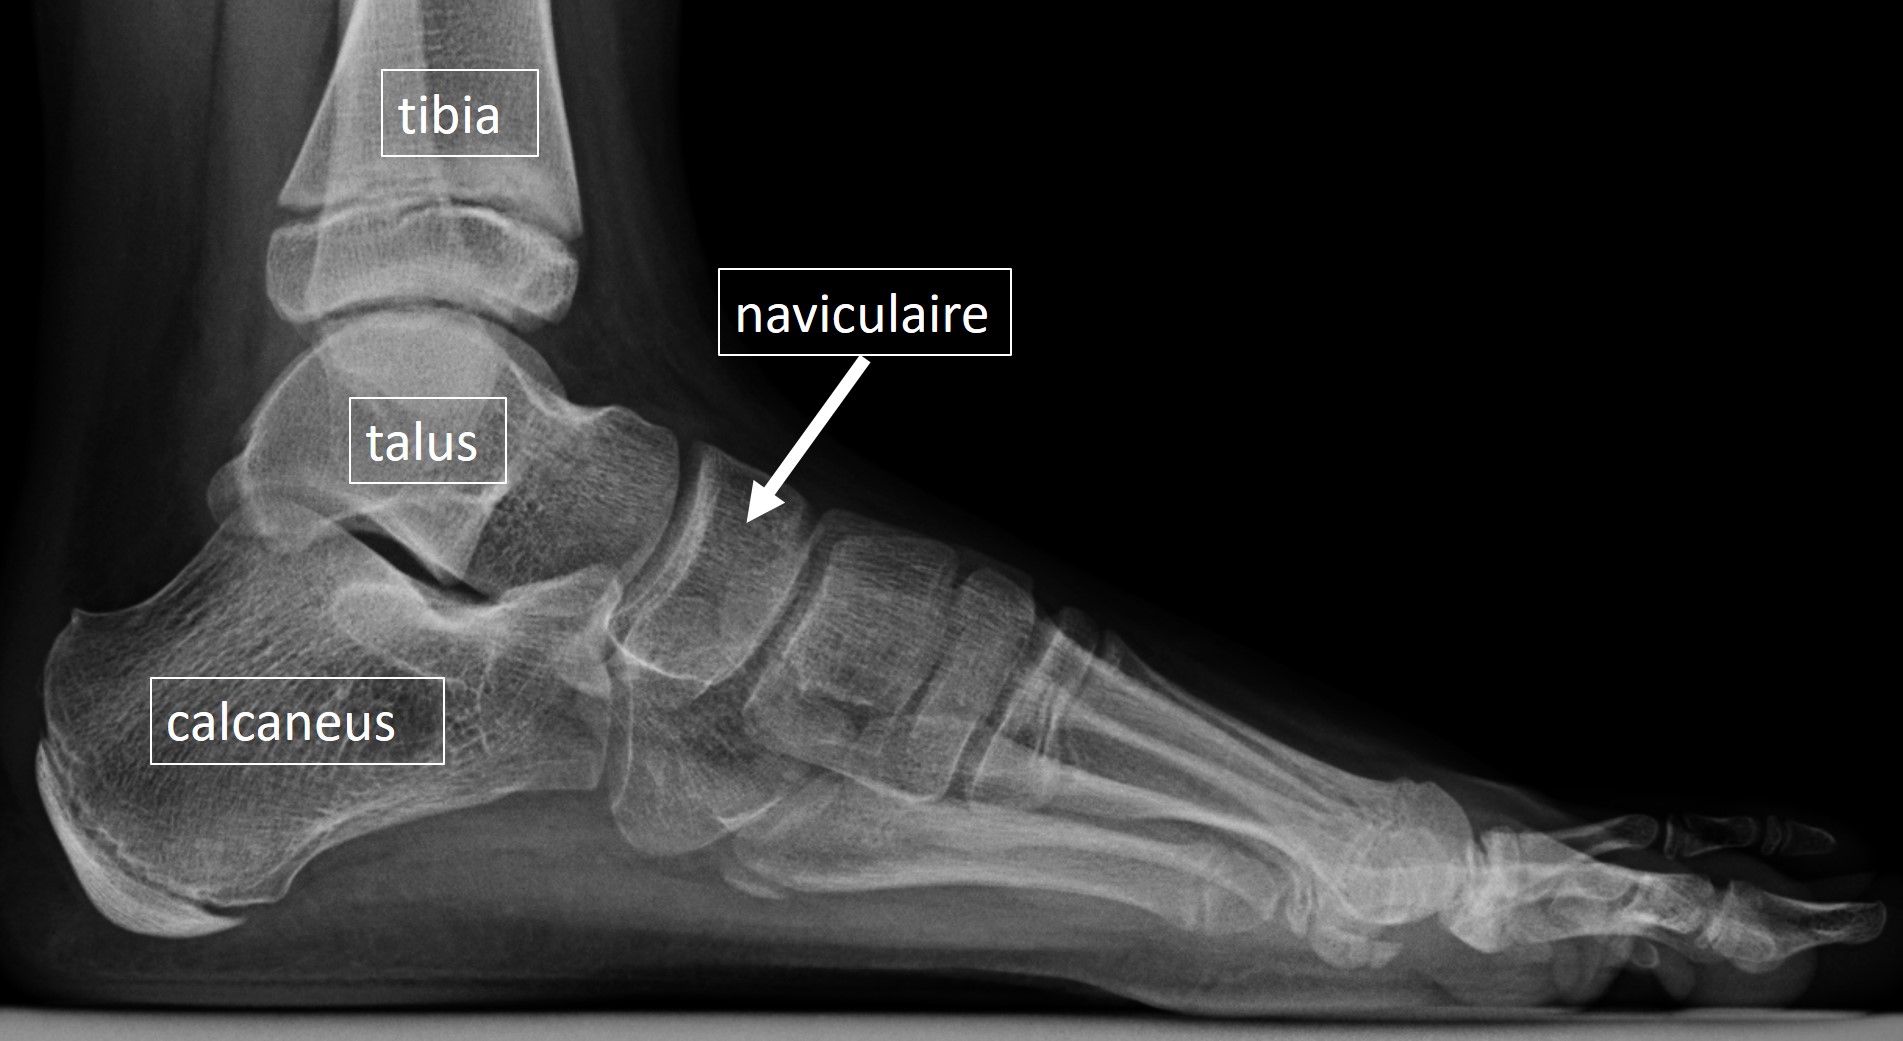

Les symptômes d'une fracture de l'os naviculaire sont semblables à d'autres problèmes qu'on peut avoir au pied suite à un choc ou un accident : simple contusion, entorse, tendinite, fracture d'un autre os du pied Figure 97.1 Une douleur du pied et de la cheville secondaire à un os naviculaire accessoire est caractérisée par une douleur à la palpation de la face médiale du pied et de la cheville

les traitements de l'os naviculaire accessoire SOS Pied Cheville. Figure 97.1 Une douleur du pied et de la cheville secondaire à un os naviculaire accessoire est caractérisée par une douleur à la palpation de la face médiale du pied et de la cheville Les douleurs sont évocatrices, situées en dedans du pied